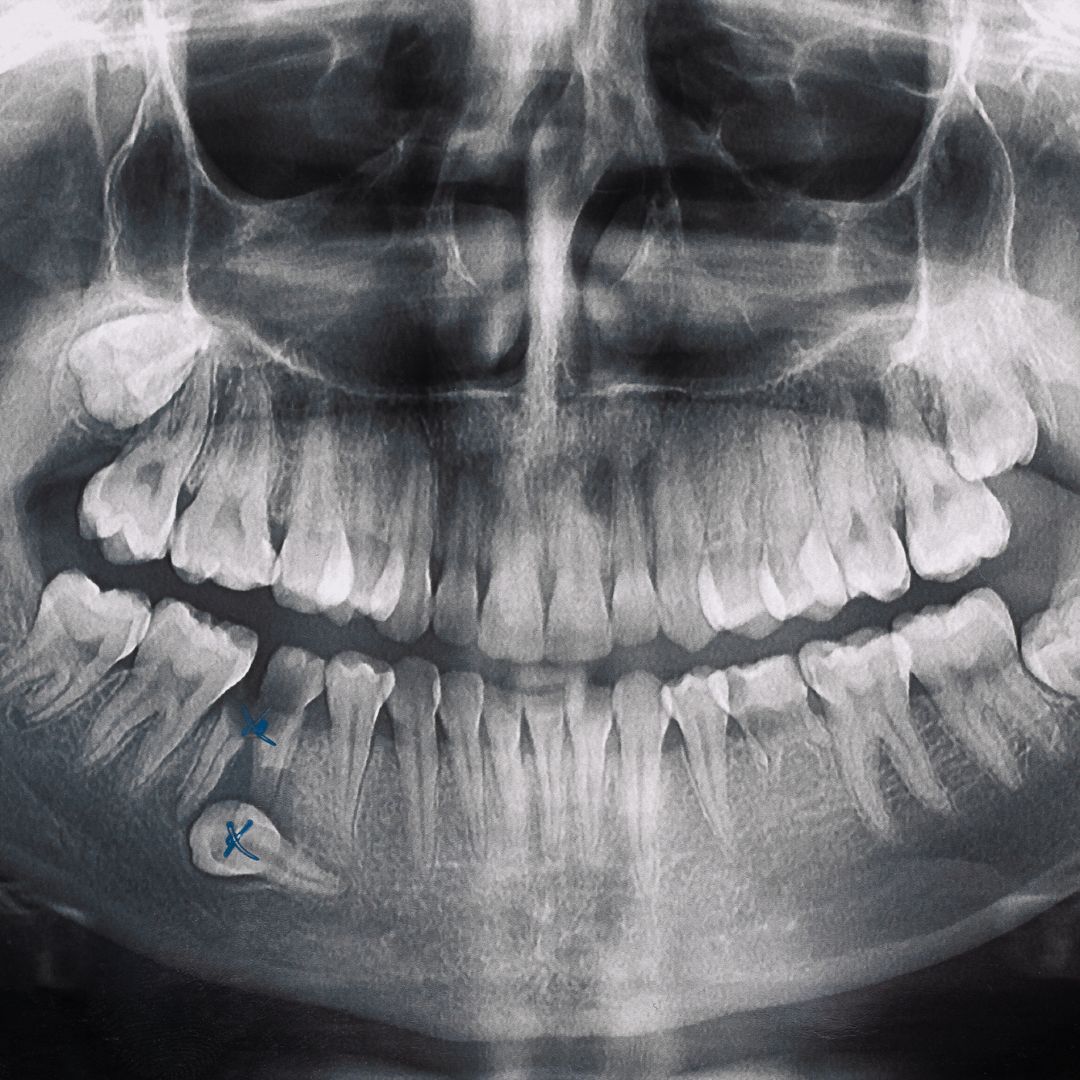

How to Read Dental X-rays for Bone Loss

Understanding your dental X-rays can help you be more engaged in your treatment. Here’s what to look for:

![Insert image of dental X-ray with annotations showing bone loss here]

Healthy Bone vs. Bone Loss

In healthy teeth, the bone level should be about 1-2mm below where the enamel meets the root (the cementoenamel junction or CEJ). On X-rays:

- Healthy bone: Appears as a white line that follows the contour of the teeth roots, with the peak of bone between teeth forming a triangle shape.

- Bone loss: Shows as a darker area where the white line of bone has receded from the tooth.

Types of Bone Loss Patterns

X-rays can reveal different patterns of bone loss:

- Horizontal bone loss: The bone recedes evenly across multiple teeth (common in generalized periodontal disease).

- Vertical bone loss: Creates angular defects or “pockets” alongside individual teeth (often more severe).

- Furcation involvement: Bone loss between the roots of multi-rooted teeth.

Remember that X-rays are just one tool your dentist uses. They’ll combine this information with clinical examination findings to determine the full extent of bone loss.